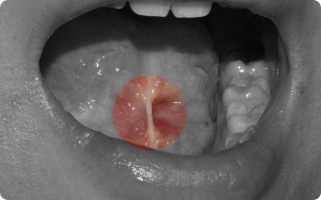

입안에도 혹처럼 불필요한 덩어리(종양)가 생길 수 있습니다.

그 중 흔히 볼 수 있는 것이 섬유종과 유두종입니다.

- 섬유종 : 잇몸, 뺨 안쪽, 혀 등에 자주 생기며, 오래된 자극(씹힘, 틀니, 교정 장치 등) 때문에 발생하는 경우가 많습니다.

- 유두종, 사마귀종 : 바이러스 감염이나 잦은 자극으로 인해 작은 사마귀처럼 돌출되는 양상을 보입니다.

대부분 양성(암 아님) 이지만, 크기가 커지거나 불편하면 제거하는 것이 좋습니다.

- 국소마취 후 병소 부위를 작게 절개하여 종양만 제거합니다.

- 필요한 경우 조직검사를 통해 정확한 진단을 확인합니다.

- 수술은 짧고 안전하게 진행되며, 회복도 빠릅니다.